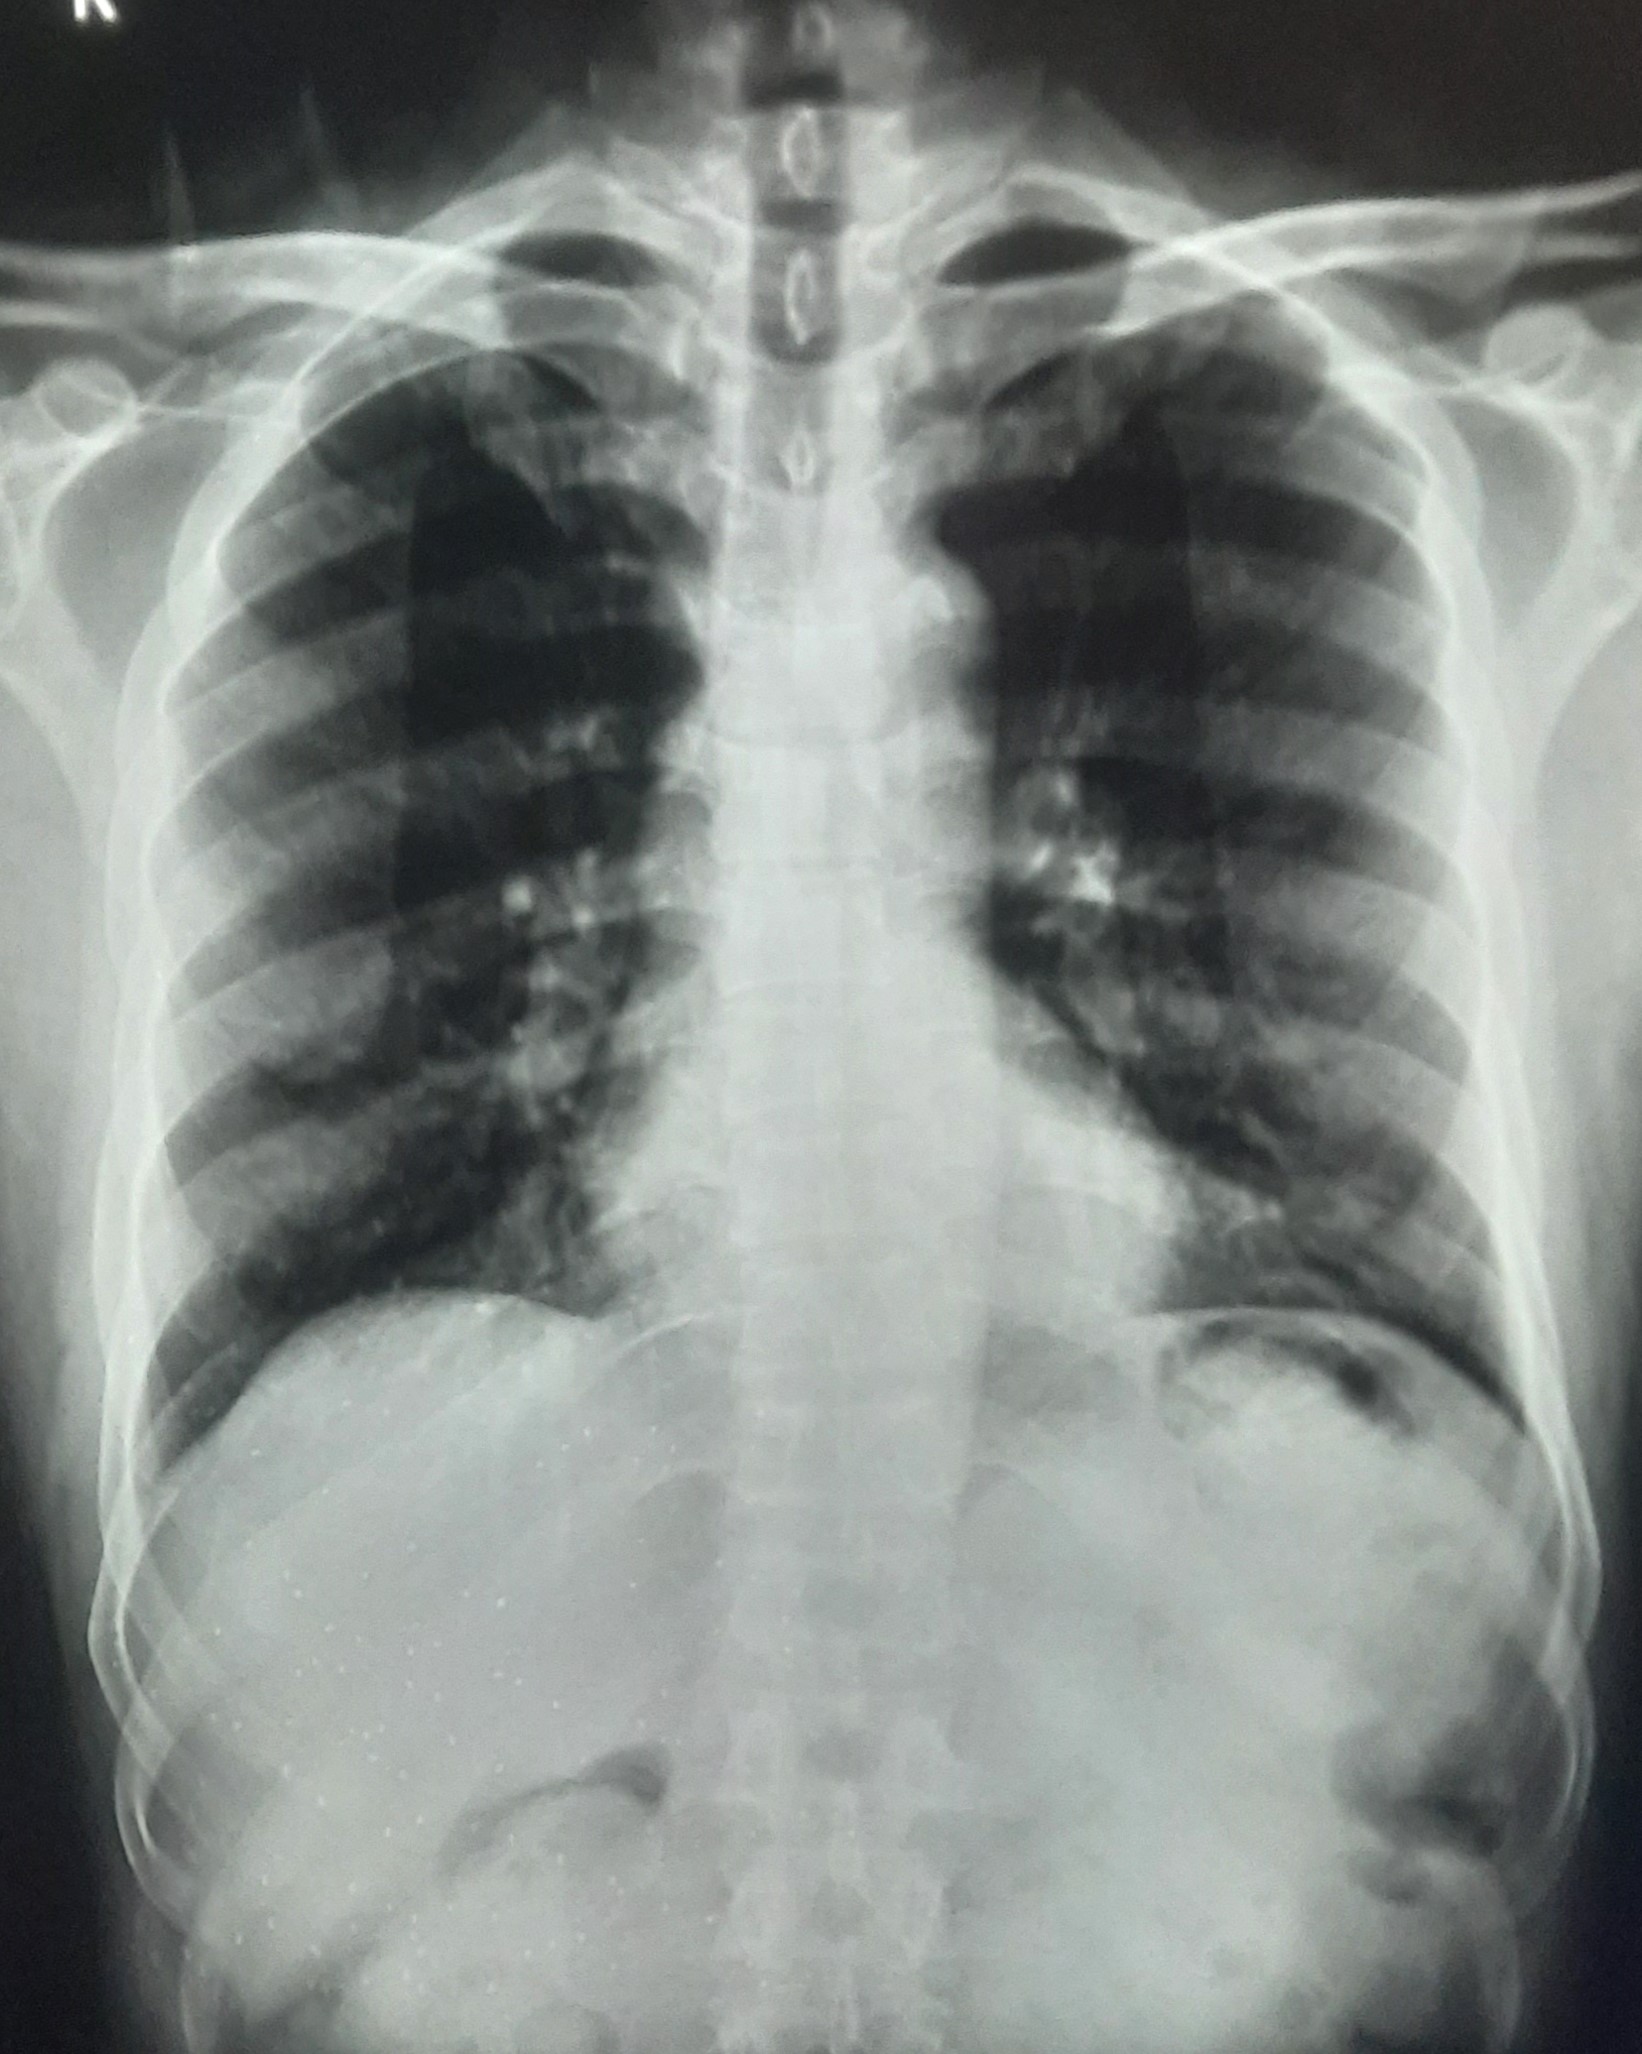

| 271 | IGGMC, Nagpur, Nagpur | P2 | 29-4201 | Abddul Qayyam | Consent taken on Paper | 75 Yrs. |

Provisional Diag : Upper Respiratory Tract Infection

Final Diag : FIBROSIS |

Non-TB Case (Confirmed) | RETICULAR OPACITIES NOTED IN PREDOMINANTLY IN UPPER ZONE OF RIGHT LUNG PARENCHYMA | Abnormality visible on x-ray |